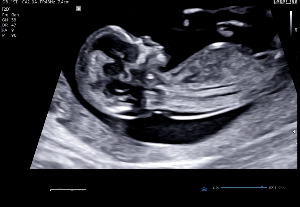

초음파 화면에 또렷하게 비친 작은 젤리곰.

몸통과 팔다리가 구분될 정도로 또렷해진 모습이었다.

길이는 2.3cm, 심박수는 184 bpm.

KakaoTalk_20250831_213642428.jpg 9주 차 귀여운 젤리곰